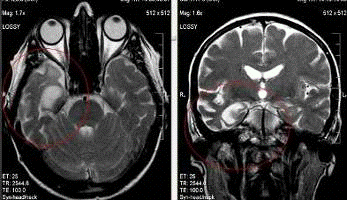

При болезни Альцгеймера, в отличие от всех других

нейродегенеративных заболеваний, максимальные изменения определяются в

гиппокампах.

Именно поэтому для диагностики используются

специальные программы высокого разрешения с прицельным исследованием височных

долей.

При этом на корональных томограммах при прицельном

исследовании височных долей определяется асимметричная атрофия гиппокампов с

истончением коры, расширением щелей Биша с двух сторон и височных рогов боковых

желудочков. Эти изменения являются наиболее ранними. Также выявляется атрофия

теменных и затылочных долей с расширением субарахноидальных пространств.

Выраженная атрофия на уровне крючка и тел гиппокампа

справа с истончением коры и белого вещества и расширением височного рога и

гиппокампальной щели.